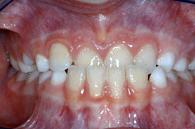

| Kreuzbiss seitlich | Zahnengstand | |